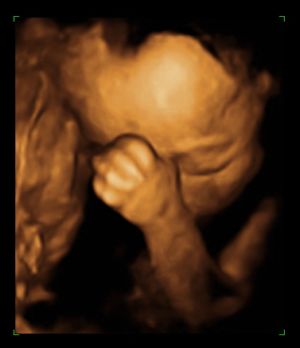

és itt van egy ultrahangos kép, sajnos a kukija pont nem látszik rajta.

Kép 19. hét, 6 nap

Kép